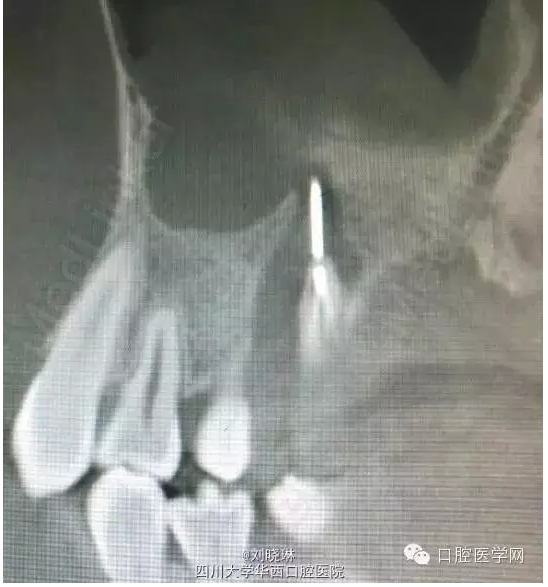

CBCT示:16牙合面大面積牙體組織密度減低影,與髓腔穿通,腭側(cè)根管內(nèi)可見高密度影像,超出根尖孔外至上頜竇,根尖周組織暗影。

討論:第一次看到對(duì)自己這么狠的人,患者14歲,為年輕恒牙,根管及根尖孔粗大,也導(dǎo)致了縫針的進(jìn)入